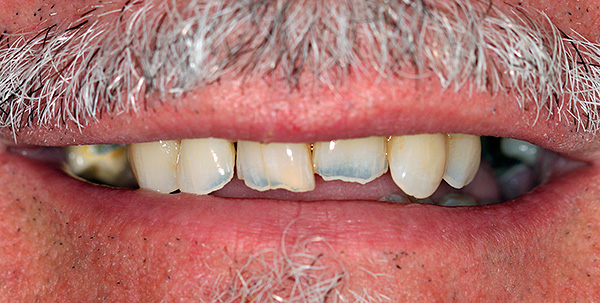

- Abrasão patológica do esmalte grave;